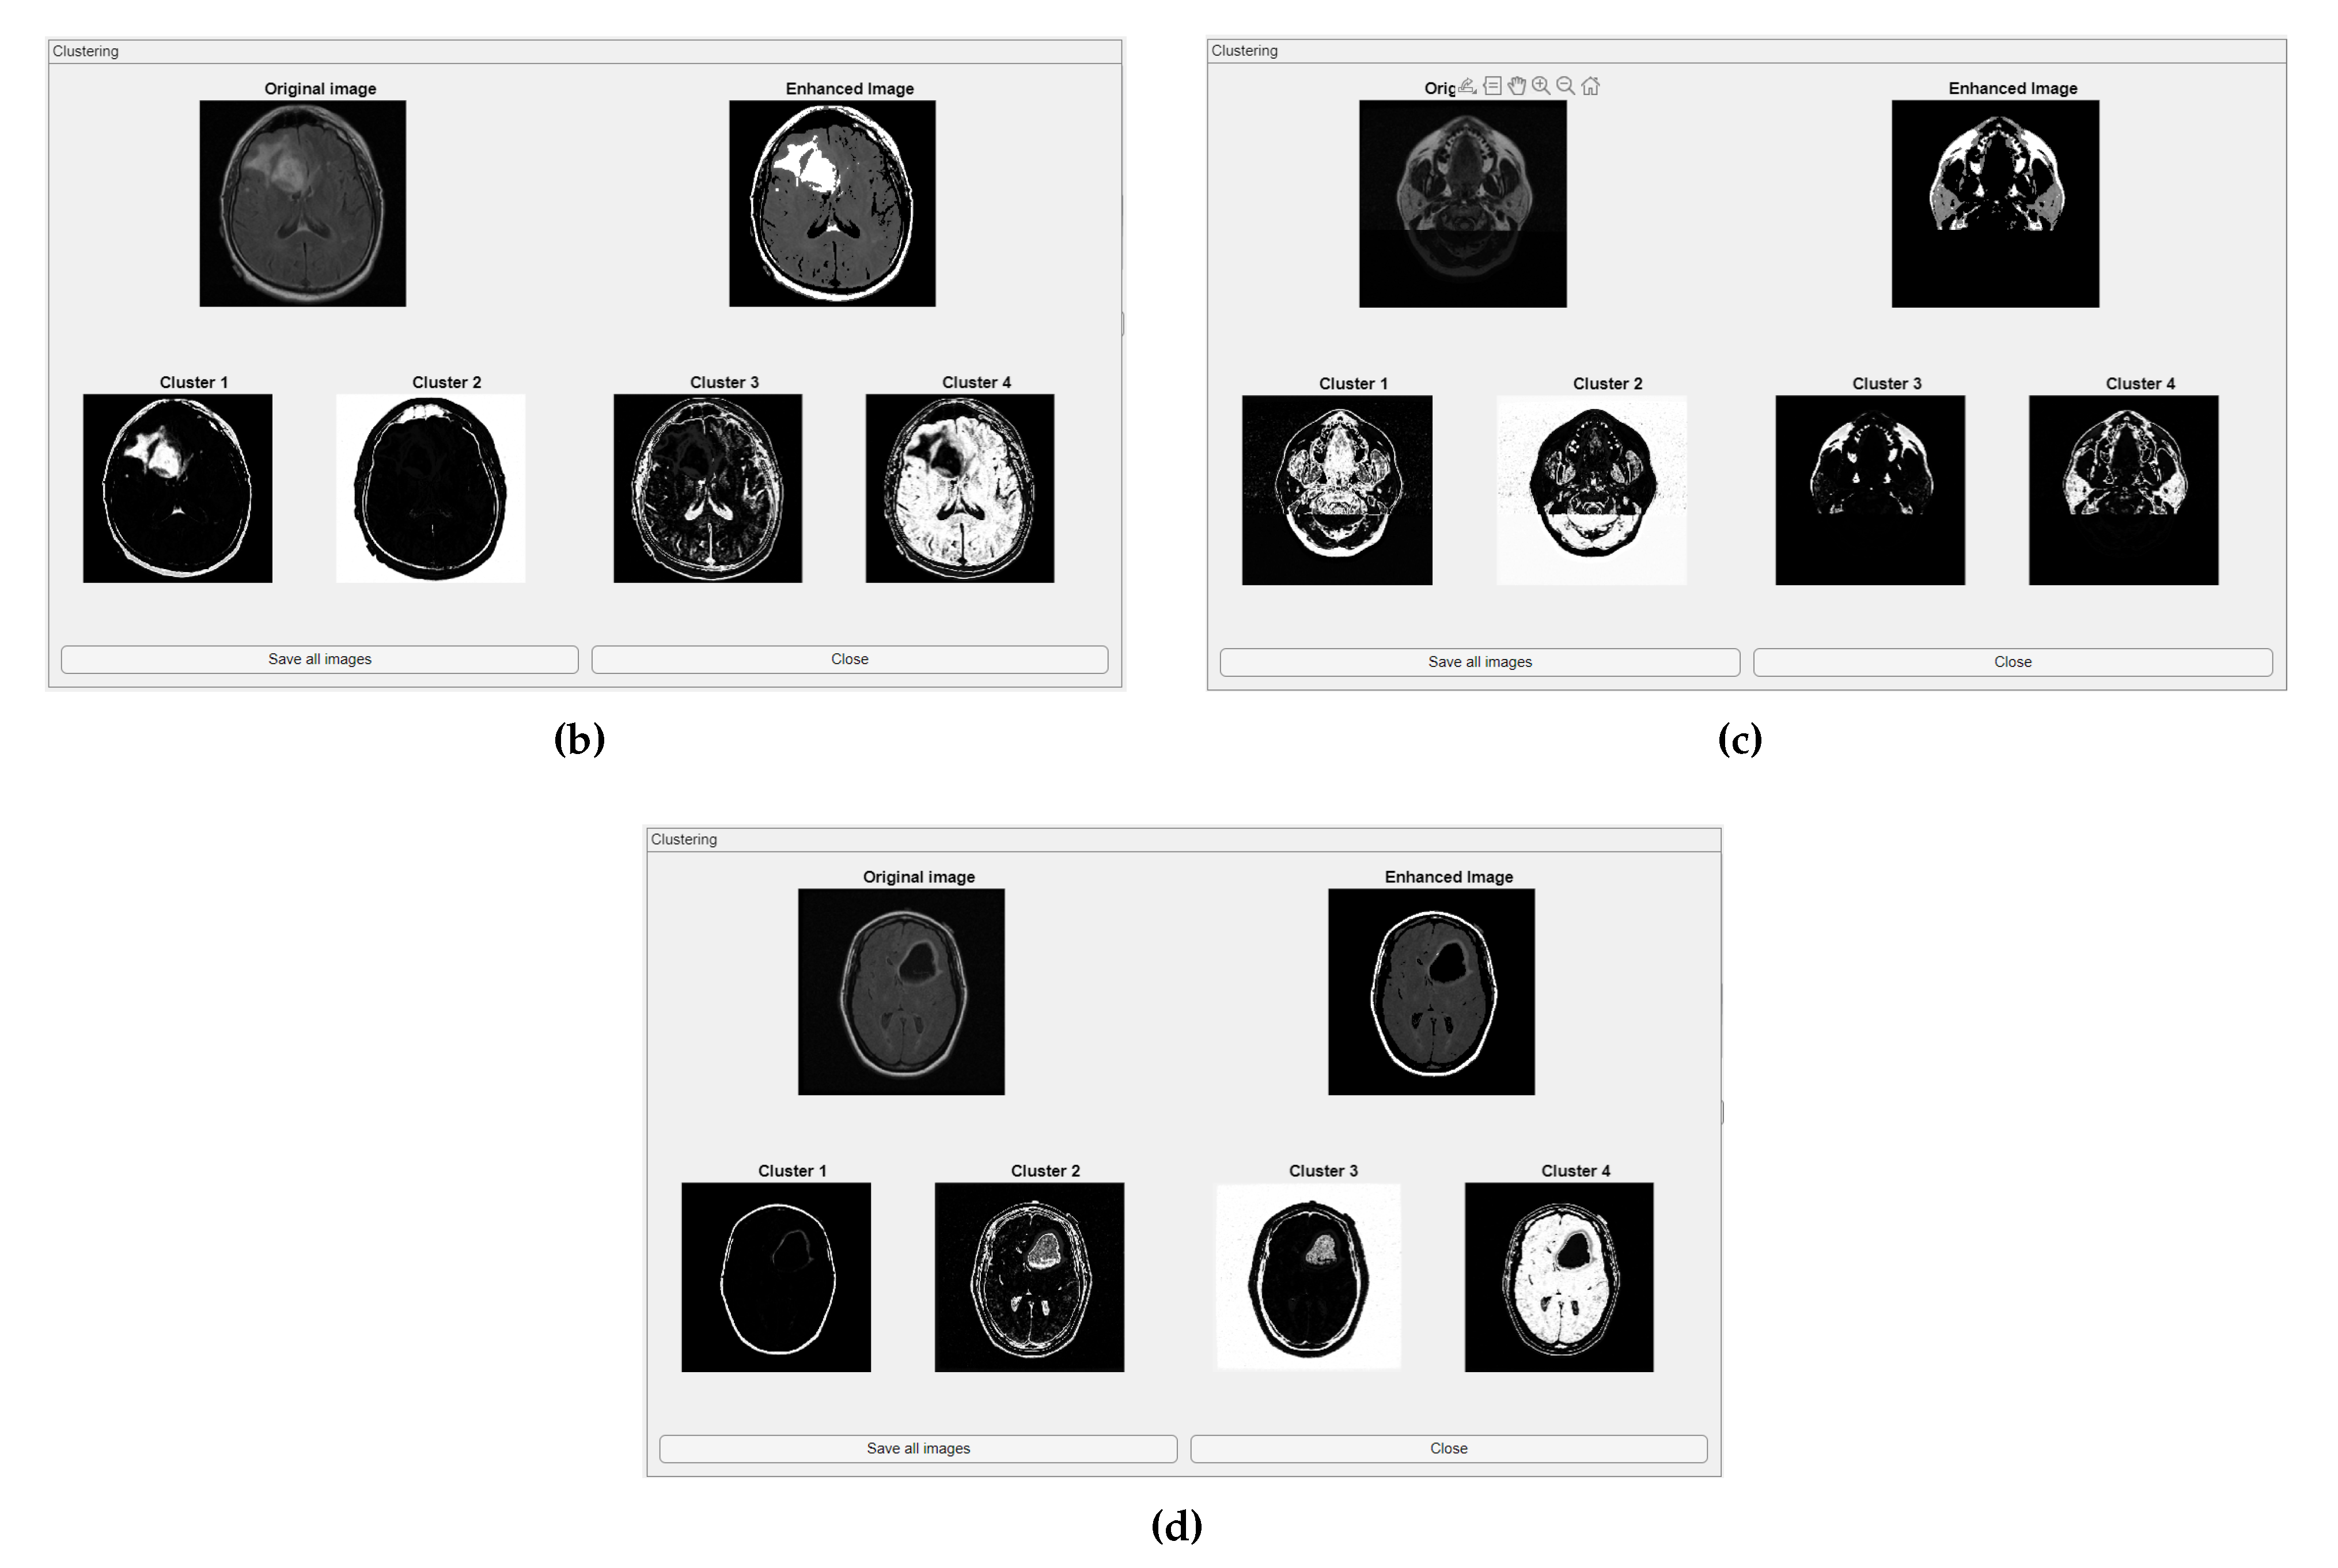

The comparative charts and visual presentation of edges allow for a detailed analysis of each algorithm’s strengths and weaknesses, offering insight into the trade-offs between edge completeness and false detection rates. Figure 4 illustrates the fuzzy C-means (FCM) clustering results obtained from the four case studies: CS1, CS2, DU1, and DU2. Each subfigure (A, B, C, and D) presents the following sequence:

-

Original Image: The initial input image from the dataset.

Enhanced Image: The result after applying image enhancement techniques to improve contrast and feature visibility, likely to support better clustering outcomes.

Clusters 1 to 4: The segmentation outputs, where the image has been partitioned into four distinct clusters. Each cluster highlights different regions based on pixel similarity, potentially corresponding to anatomical structures, tissues, or specific features of interest within the medical images.

Key Observation: Figure 4 and Figure A1 collectively showcase the clustering module’s capacity to aid in visual discrimination and structural interpretation across the studied medical cases.

Figure 4. Clustering with fuzzy C-means (FCM) results within iMIA platform: The clusters emphasize various structural and textural components, with some clusters isolating specific regions with clear edges and others focusing on more homogeneous areas. The segmentation reveals critical areas with varying intensity patterns, possibly indicative of different tissue types or pathological regions: TCGA_CS_4941_19960909_3 (CS1) (additional results are shown in Figure A1).

Figure A1. Clustering with fuzzy C-means (FCM) results within iMIA platform. (b) TCGA_CS_4941_19960909_14 (CS2), (c) TCGA_DU_5872_19950223_1 (DU1), (d) TCGA_DU_5872_ 19950223_35 (DU2) (refer to the image (a) CS1 result in Figure 4).